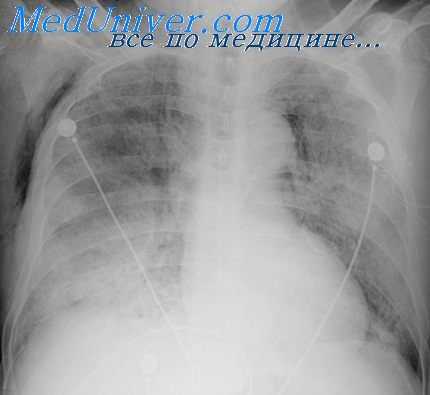

В одной серии наблюдений, включающей 88 больных с баротравмой легких, газ поступает в разорванные легочные сосуды, а затем в системную циркуляцию крови, вызывая в 75% случаев объективные и субъективные проявления нарушений ЦНС [Elliott et al., 1978].

Газ, который проникает в разорванные сосуды перегородок альвеол, далее мигрирует через легочные вены в левое предсердие и левый желудочек, а затем изгоняется в систему циркуляции в вид вспененных частиц, которые распределяются по кровеносному руслу в соответствии со степенью их плавучести. В обычном вертикальном положении тела весь объем эмболического газа поступает в мозг, в то время как в обратном положении с поднятыми вверх ступнями эмболизируются преимущественно коронарные сосуды.

В противоположность неврологической форме болезни декомпрессии, возникающей при субнасыщенном погружении, основным органом-мишенью при дисбарической артериальной газовой эмболии является головной мозг, признаки его дисфункции доминируют в клинической картине заболевания. Эмболизация газом артерий и артериол вызывает как дистальную ишемию, так и прямое повреждение эндотелия в месте обструкции, которое не опосредованно исключительно гипоксией или ишемией.